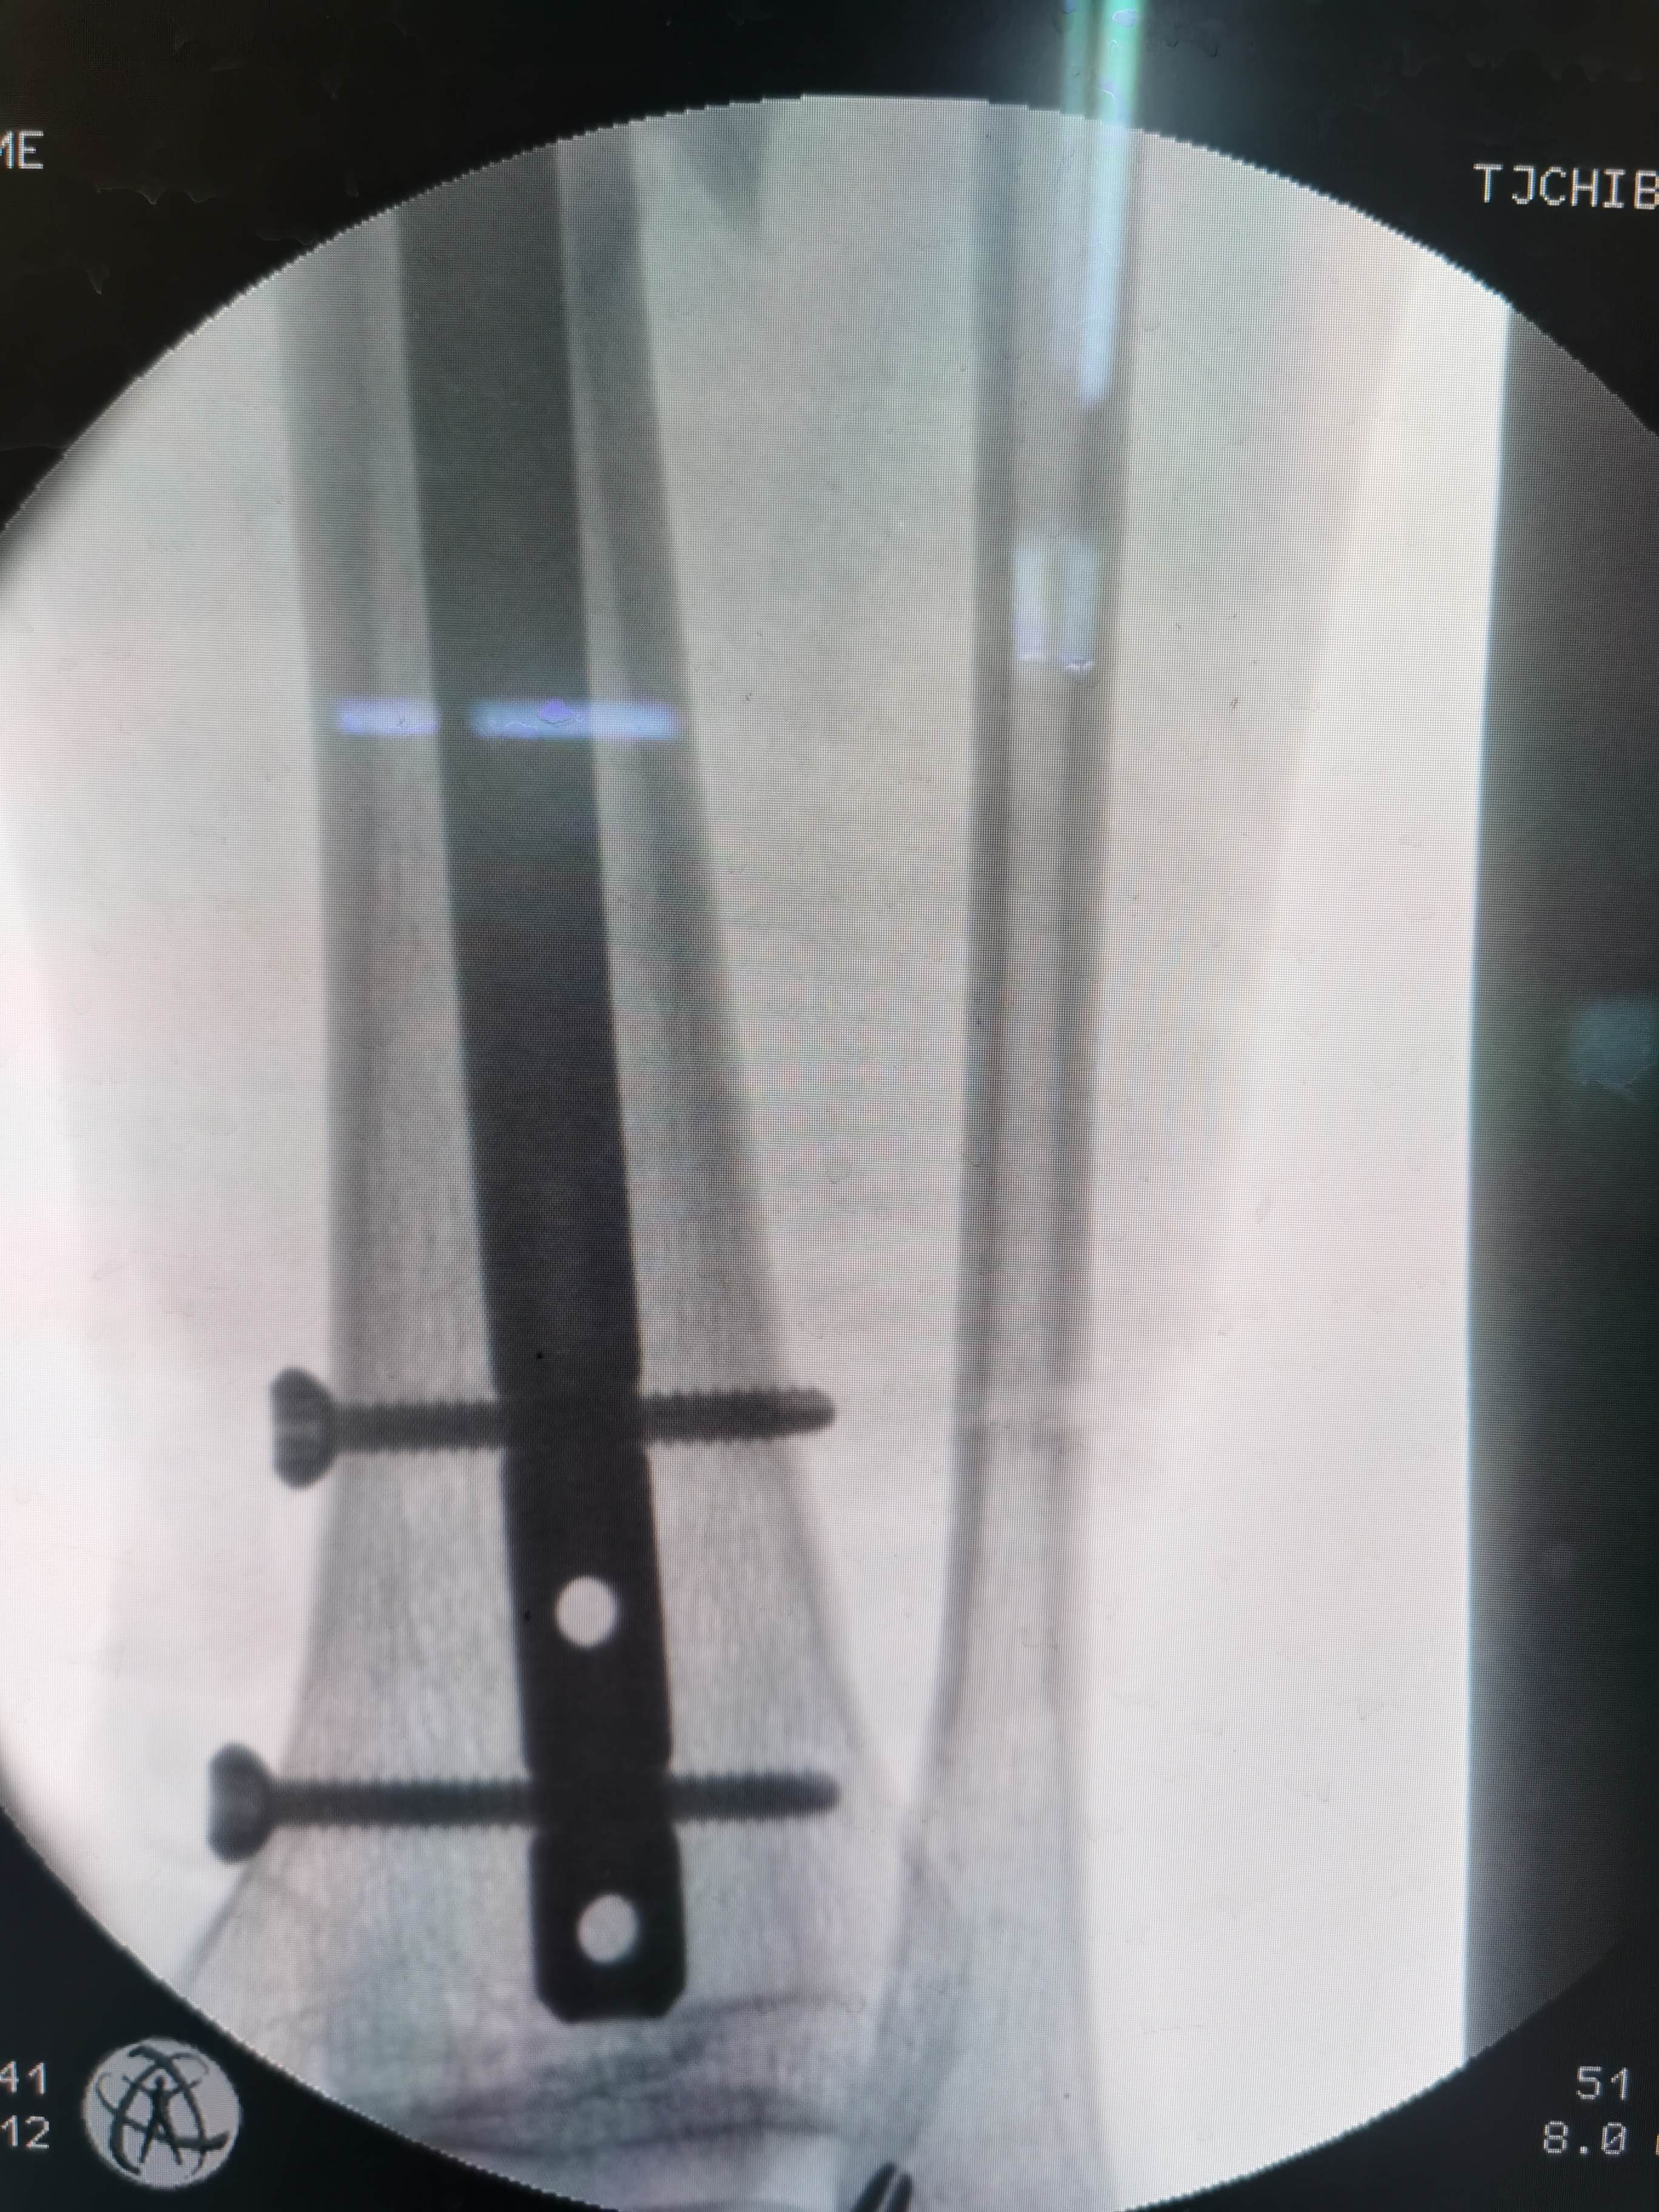

术中透视远端正位

患者男,53岁,因外伤致右胫骨中段粉碎性骨折。内踝前方有片状皮肤擦伤。入院后完善术前检查,给予石膏托固定,消肿处理。评估手术风险后,在腰硬联合麻醉下行右胫骨骨折闭合复位交锁髓内钉固定。术中屈曲膝关节,传统髌韧带入路,锥形开口后置入导针,金手指插入复位,扩髓,植入10mmx340mm髓内钉,远近端锁钉。手术顺利,因盲打远端锁钉,反复调整了几次,手术时间一个半小时,未使用止血带,出血约100m1。